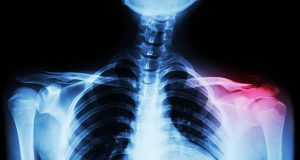

الرئيسية » أفضل برنامج علاج طبيعي للتعامل مع كسر الترقوة